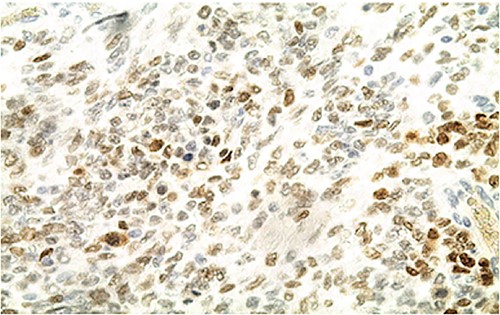

Biologically, the CA 125 tumor marker was at 126.2 IU/ml. The patient underwent a left adnexectomy and an omentectomy (small omentum). Macroscopically, the ovarian mass was smooth on the surface and fleshy on section with the presence of necrotic and hemorrhagic changes. On the histological level, the tumoral proliferation presents a diffuse architecture formed by sheets and clusters separated by fine fibrous septa. Tumor cells are rounded, small, and monomorphic with hyperchromatic, finely nucleolated nuclei and reduced cytoplasm. Mitotic activity is high (36 mitoses/10 HPF) (Figs 3 and 4). The samples taken from the small omentum were tumorous. An immunohistochemical study was carried out and showed diffuse positive expression by tumor cells of Vimentin, and focal by antibodies (Cytokeratin AE1/AE3, EMA, CD99, WT1, Inhibin, and SALL4) and an absence of expression by antibodies (CD45, Chromogranin, PAX8, and AFP) (Figs 5–7).

IHC: tumor cells show a nuclear strong expression of p16 (x400).